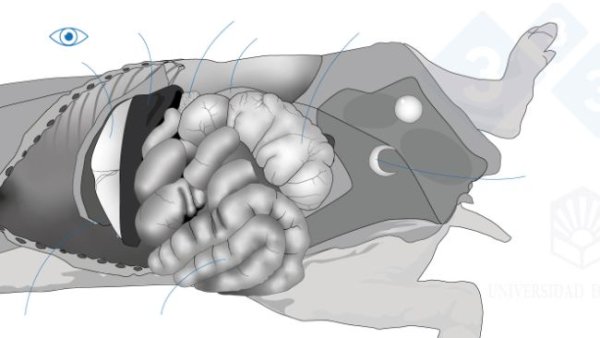

In diesem zweiten Teil behandeln wir das Herauslösen von Zunge, Luftröhre, Lunge und Herz in einem Stück. Wir entnehmen die Organe der Bauchhöhle, sowohl den Verdauungs- als auch den Harn- und Genitaltrakt. Im Kopf legen wir die Nasenmuscheln, das Großhirn und das Kleinhirn frei.